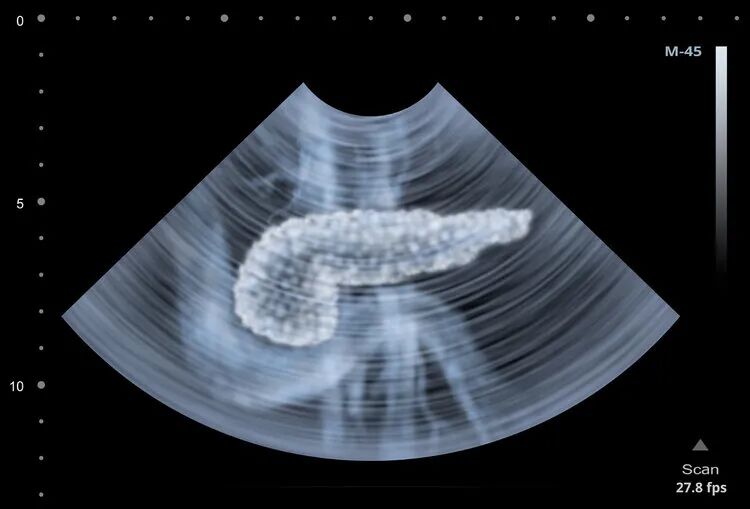

其次,胰腺癌的早期诊断十分困难,如果做B超,容易受腹壁脂肪厚度和胃肠气体的影响,导致假阴性。CT、MRI等检查手段比较精准,但价格比B超贵,患者会考虑性价比,拒绝做,最终错过早期诊断的机会。